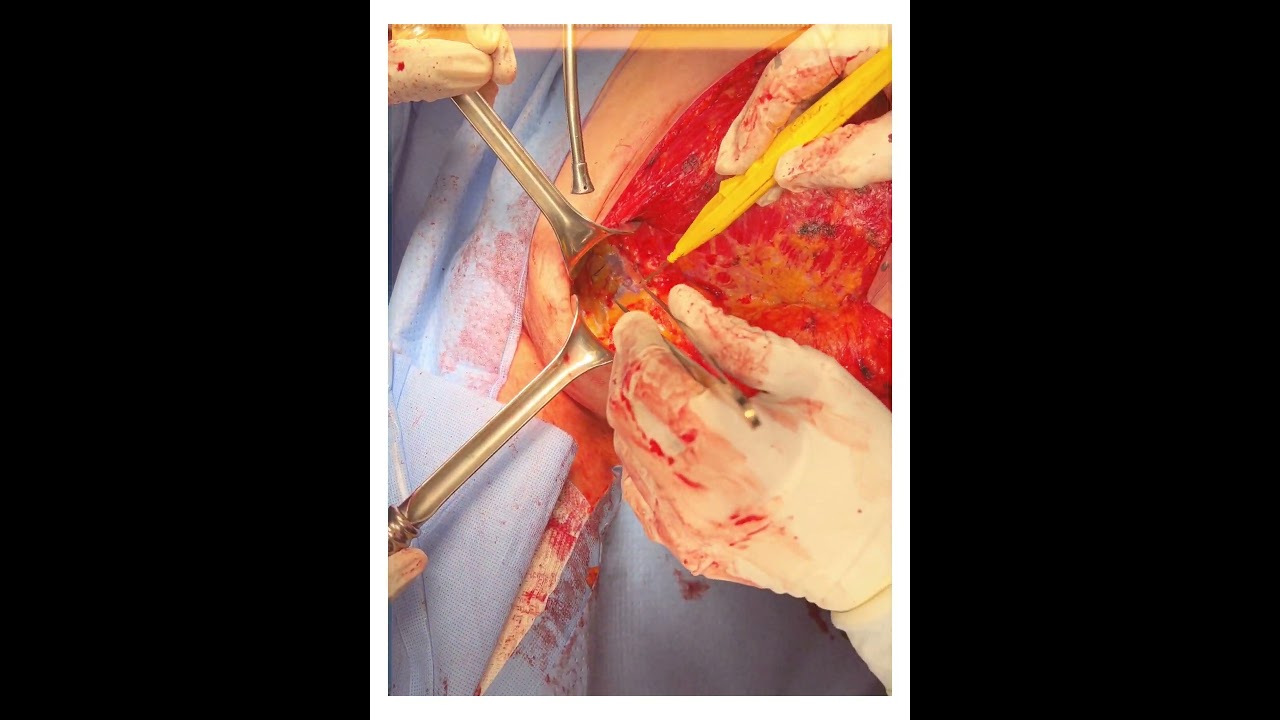

Cirugía ginecológica y obstetrica de alta complejidad

Cirugía Robótica Ginecológica